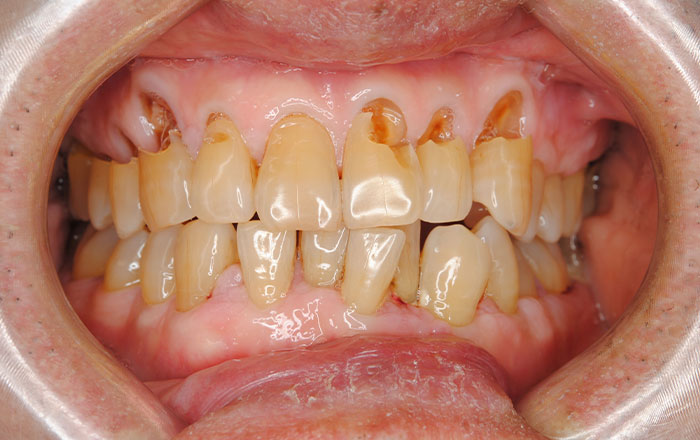

1)歯周病が進行している

歯周病が進行し、歯の根元の象牙質という部分が露出してしまうと、知覚過敏の症状が出ます。

象牙質には歯髄と呼ばれる神経につながる無数の穴(象牙細管)があいているため、象牙質の穴を通して、受けた刺激が神経に伝わり痛みを感じてしまいます。